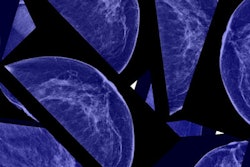

The number of DCIS diagnoses in recent years has increased due in part to improvements in mammography screening. While clinical outcomes in these cases are usually favorable, the researchers said that up to 40% of women develop a second breast cancer after DCIS, 28% of which are invasive breast cancers.